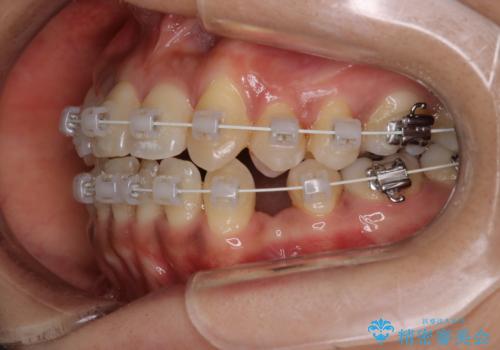

- 審美装置

- 2年2ヶ月

- 10-30回

抜歯矯正のため2年はかかってしまいましたが、きれいに並び患者様にも満足頂きました。